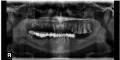

Слетел верхний мост на штифтах из 11 зубов, под ним много сгнило. Подскажите, какие зубы удалять? Как недорого протезировать? Какое состояние под нижним мостом ― может там тоже всё гниёт?

• Однозначно могу сказать, что несъемная конструкция на верхней челюсти у Вас уже не получится. 12, 13, 17 корни зубов однозначно удаляются, 28 также подлежит удалению. Все остальное необходимо исследовать очно на наличие подвижности. На нижней челюсти также недопустимый мостовидный протез, большие пролеты и консоль, что однозначно является неправильной ортопедической конструкц читать далее